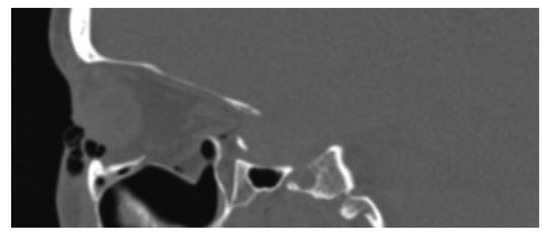

Figure 4.

Intra-operative coronal CT scan of posterior ledge and precise relationship to the titanium implant.